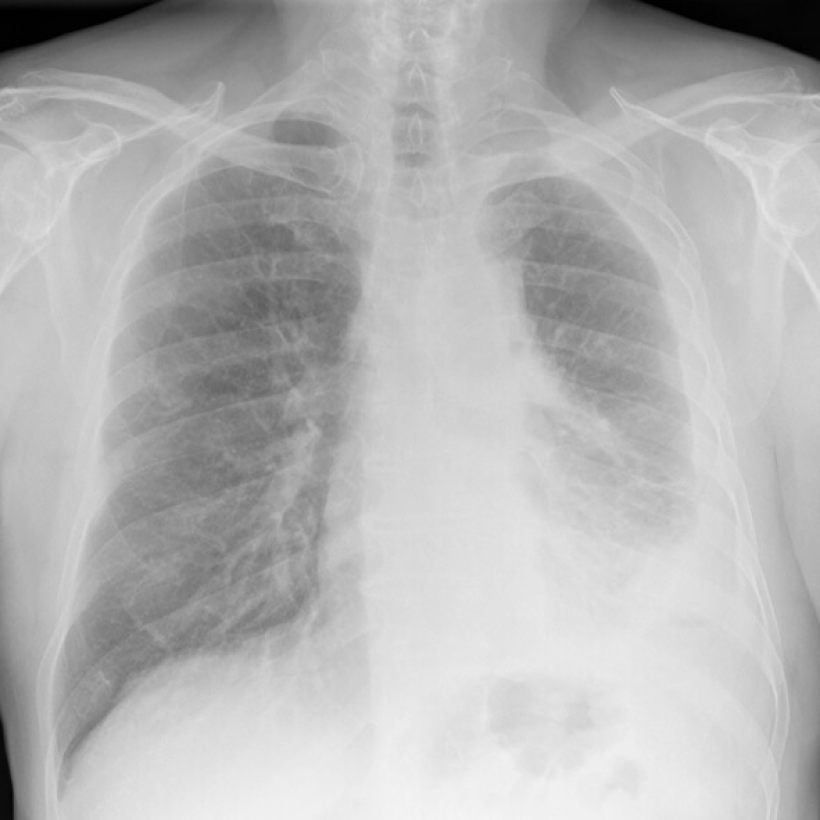

Digital chest x-ray of advanced malignant mesothelioma on left.

Lighter and hazy areas on the X-ray show possible mesothelioma tumors.

On a chest X-ray, pleural or pericardial mesothelioma tumors appear as wispy white areas around the lungs, while calcified tumors appear bright white. Bones appear white and healthy lungs are dark. Most abnormalities appear as lighter areas that are hazy or solid.

Tumors and scarring may distort chest anatomy. Compressed lungs or a raised diaphragm can be visible on an X-ray.

X-rays are 2D, making it hard to determine if a tumor is in the lung, pleura or the mediastinum around the heart. Additionally, X-rays don’t clearly show peritoneal or testicular mesothelioma. CT, MRI and PET/CT scans offer more detailed images for all mesothelioma types.